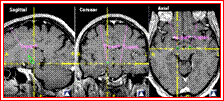

神经导航系统Surgiscope:1999-2000年我院在省内首先引进最先进的神经导航设备,已广泛应用于大脑深部肿瘤、多发性肿瘤、颅底肿瘤、脑血管畸形等各种颅内疾病的微创手术,手术具有定位精确、创伤小、恢复好、肿瘤全切率高等等特点。该技术成为我科治疗神经系疾病的一项重要手段和特色,在华东地区产生一定的影响力,居国内领先水平。至今已经数百例患者得益,获得好评。